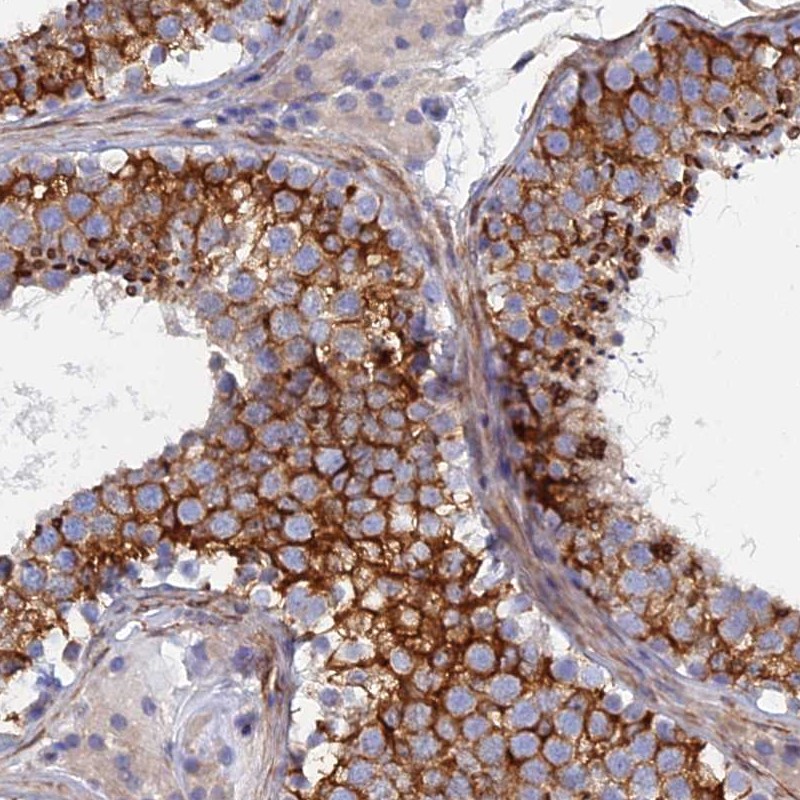

Immunohistochemical staining of human testis shows strong cytoplasmic positivity in cells in seminiferus ducts.